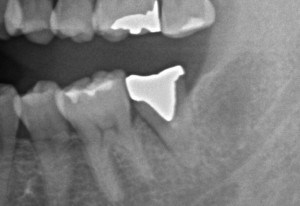

この歯から膿が出るとの事で拝見させて頂くことになりました

ポケットが10mmを超えており、嫌な予感。

クラウンを外してみるとマイクロで破折線が見えたので抜歯の必要があると患者さんにお話ししました。

この写真だと解りにくいですが、割れ目に沿って不良肉芽が・・・

ドナーサイトの8埋伏部・・・